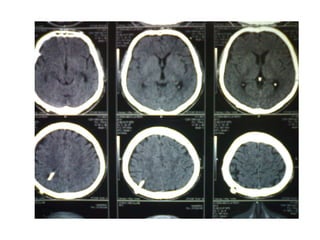

Investigation U ltrasonography to visualize the ventricular system(when the anterior fontanelle is patent). Also for antenatal diagnosis CT and /or MRI of the head; it is important to exclude any abnormal masses and to study the size and the shape of the ventricles, and some time needs contrast study.  LP in cases of communicating hydrocephalus for both diagnostic and therapeutic…..( NPH)

Investigation U ltrasonographyto visualize the ventricular system(when the anterior fontanelle is patent). Also for antenatal diagnosis CT and /or MRI of the head; it is important to exclude any abnormal masses and to study the size and the shape of the ventricles, and some time needs contrast study. LP in cases of communicating hydrocephalus for both diagnostic and therapeutic…..( NPH)